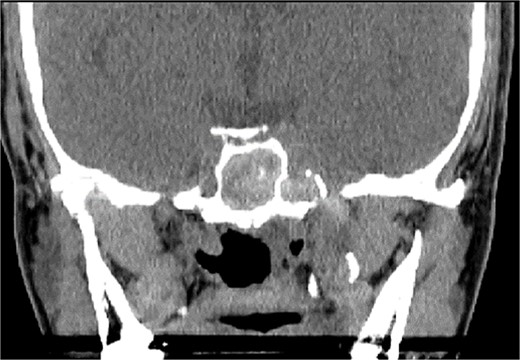

A 36 years-old man with no previous history of medical disease presented to the otolaryngology clinic with a chief complaint of headache that was associated with pressure feeling mainly in the occipital area. He also reported a post-nasal drip. The patient underwent a non-contrast paranasal sinus CT scan (Fig. 1) that demonstrated an isolated sphenoid sinus homogenous opacification, most likely representing sphenoid fungal ball. A decision was made to proceed with endoscopic sphenoidotomy (Fig. 2) to clean and remove the debris, which confirmed the diagnosis of sphenoid sinus fungal ball.

Intra-operative (A and B) endoscopic sphenoidotomy showing fungal debris, with post-operative examination (C) showing clean wide sphenoid sinus free from fungal debris.